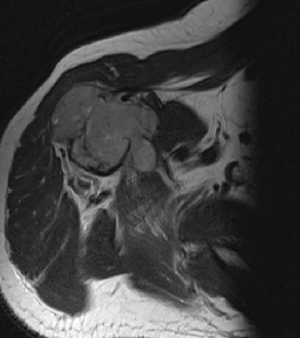

МР-диагностика новообразований конечностей (суставы, кости, мягкие ткани)

- Визуализация патологических изменений в конечностях и суставах

- Оценка и стадирование первичного их поражения, выявление рецидивов

- Дифференциальная диагностика метастазов и других заболеваний костных структур, мягких тканей